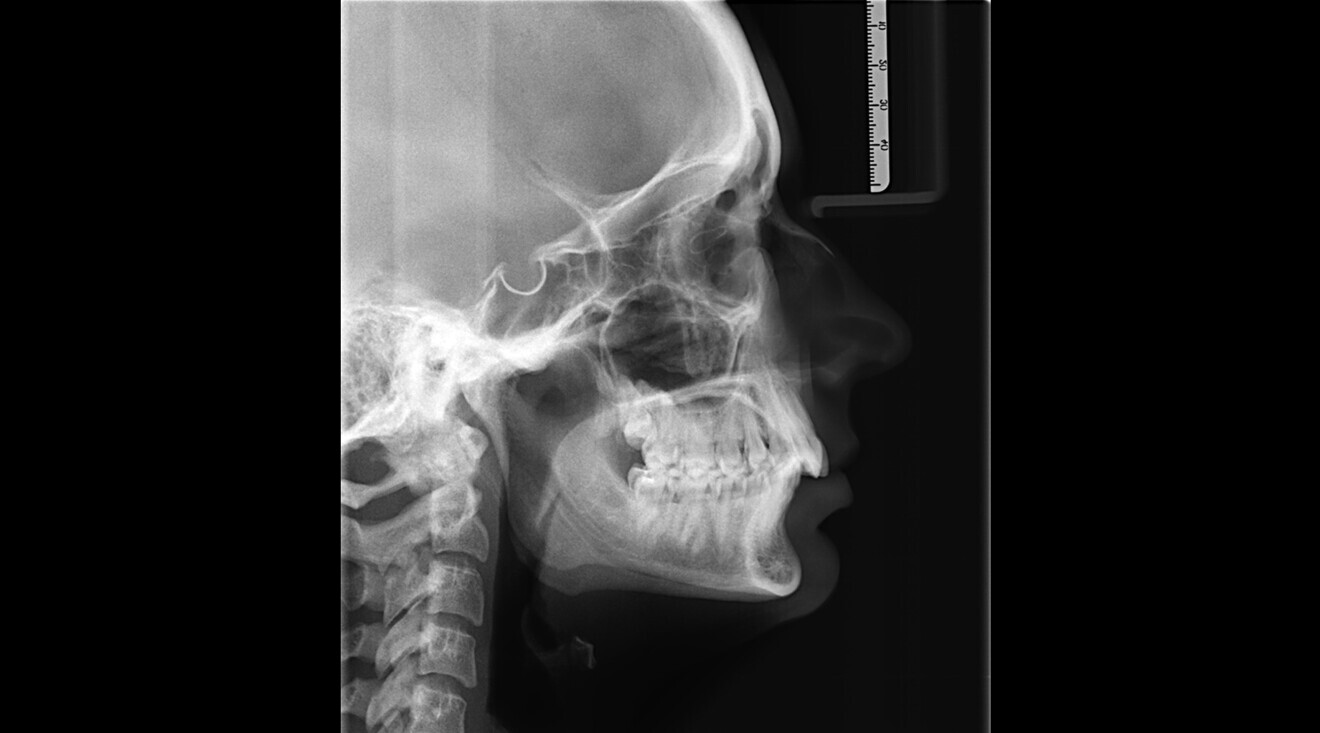

Fig. 3: Cephalometric radiograph.